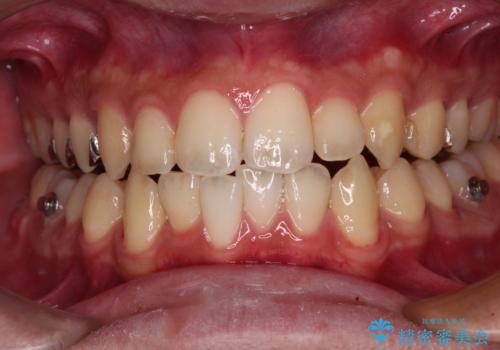

前歯のクロスバイト インビザラインによる矯正治療

- 上下のクロスバイトと前歯のデコボコを気にして来院された患者様です。

インビザラインを用い、IPR(歯と歯の間を削る)と歯列全体を拡大させることで、歯並びを整えていくこととしました。

インビザライン特有の、治療後半に奥歯が咬み合わないという事象が長引きました。

咬み合わないときの対処方法は色々とありますが、ゴムかけなどを活用して噛めるようにしました。